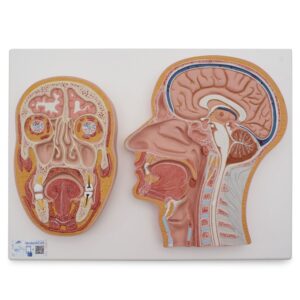

UK 3B Scientific manufacture anatomical models and teaching aids for medical education. 3B Scientific manufacture Medical Simulators, Human anatomy models and charts for universities, schools & health boards.

With competitive value and quality products 3B Scientific equipment has become very popular. Their smart app and other advanced technologies allows students more anatomical information and learning than ever.

UK 3B Head Musculature Model